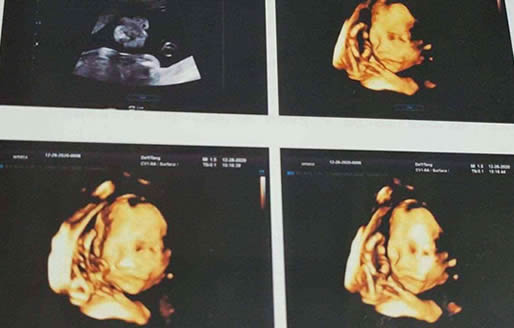

四维彩超high1和high2是不能看男女的,四维彩超右上角的high1和high2主要是代表了超声检查仪的质量,所以和胎儿性别其实并没有什么关系。...

1.四维彩超high1和high2是不能看男女的,四维彩超右上角的high1和high2主要是代表了超声检查仪的质量,所以和胎儿性别其实并没有什么关系。

2.根据检查的目的不同,所以对于四维彩超的仪器也会有调整,这种情况就会出现检查单上high1和high2的不同标识,但由于四维彩超清晰图片的缘故,所以检查单上很多东西都会和孩子性别扯上关系,比如high1和high2,但他们可和性别没有关联哦!所以大家也不要太过于纠结四维彩超上的数据和男孩女孩是否有关系。